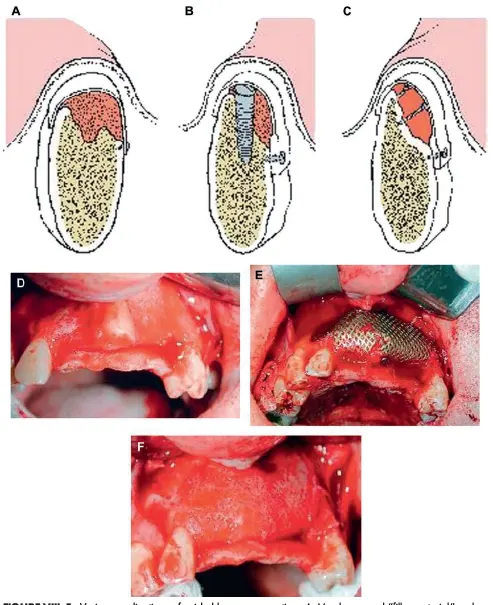

شکل VIII‑5. کاربردهای مختلف بازسازی هدایتشده استخوان

A: از غشاء و مادهٔ پُرکننده مانند استخوان آلوژن برای افزایش حجم برجستگی استخوان استفاده شده است.

B: همان روش نشاندادهشده در تصویر A، با این تفاوت که ایمپلنت بهصورت همزمان در محل قرار داده شده است.

C: غشاء بهوسیلهٔ پیچها حمایت میشود تا فضای زیر گرافت حفظ شود و استخوان بتواند آن را پُر کند.

D: برجستگی تحلیلرفتهٔ قدامی فک بالا.

E: توری تیتانیومی حاوی گرافت در ناحیهٔ قدامی فک بالا قرار داده شده است.

F: شکل استخوان پس از برداشتن توری نشان داده شده است.